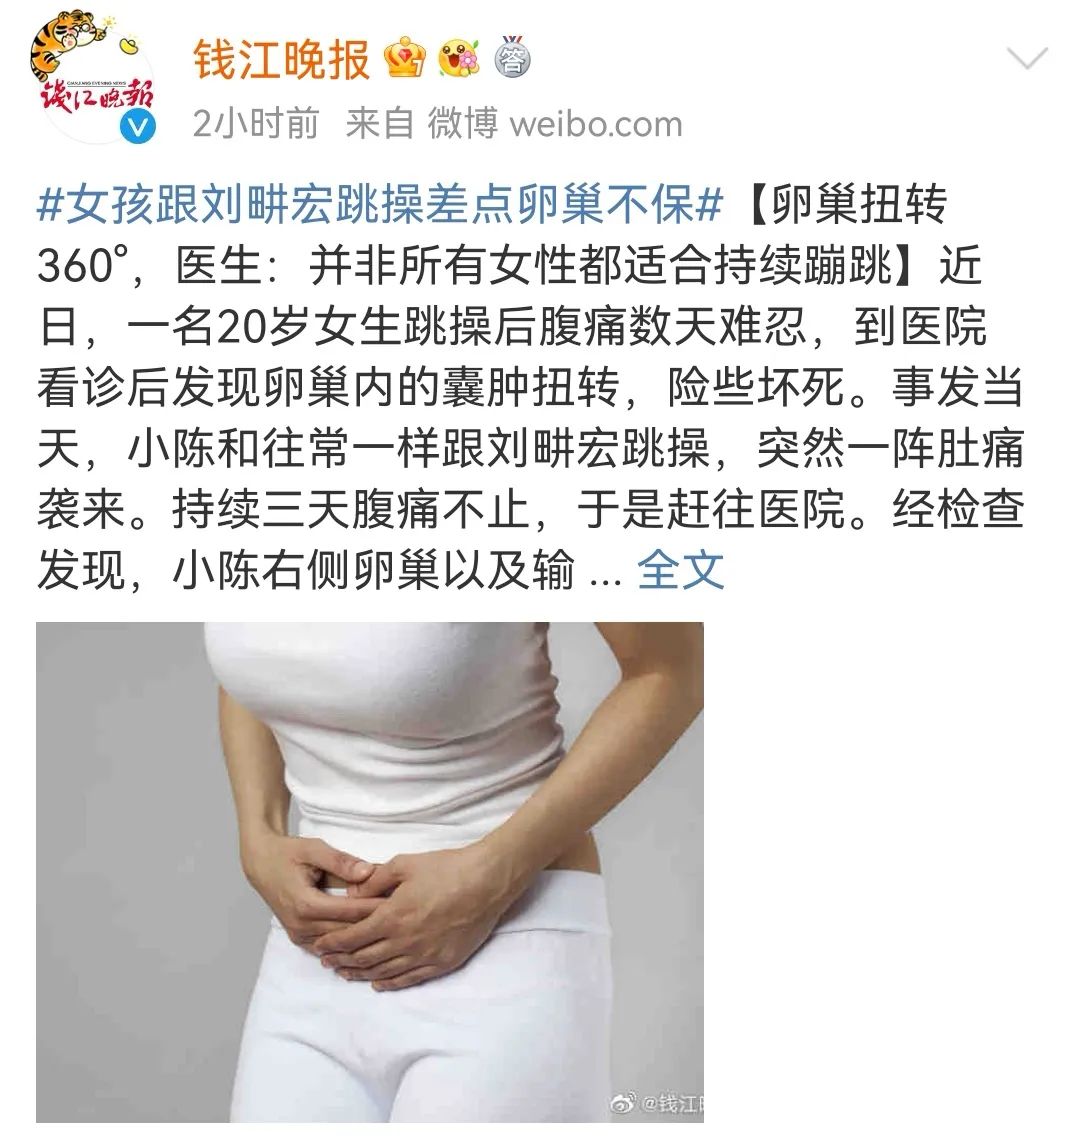

卵巢扭转是指卵巢及其输卵管附件在体内发生扭转。这是一种妇科急症,严重时可危及卵巢健康,甚至生命。症状

卵巢扭转的症状可能因人而异,但常见症状包括:- 突发的下腹痛,通常是一侧的

- 疼痛可能很剧烈,呈绞痛或痉挛样

卵巢扭转的确切原因尚不清楚,但可能与以下因素有关:- 卵巢肿大或囊肿

- 剧烈运动